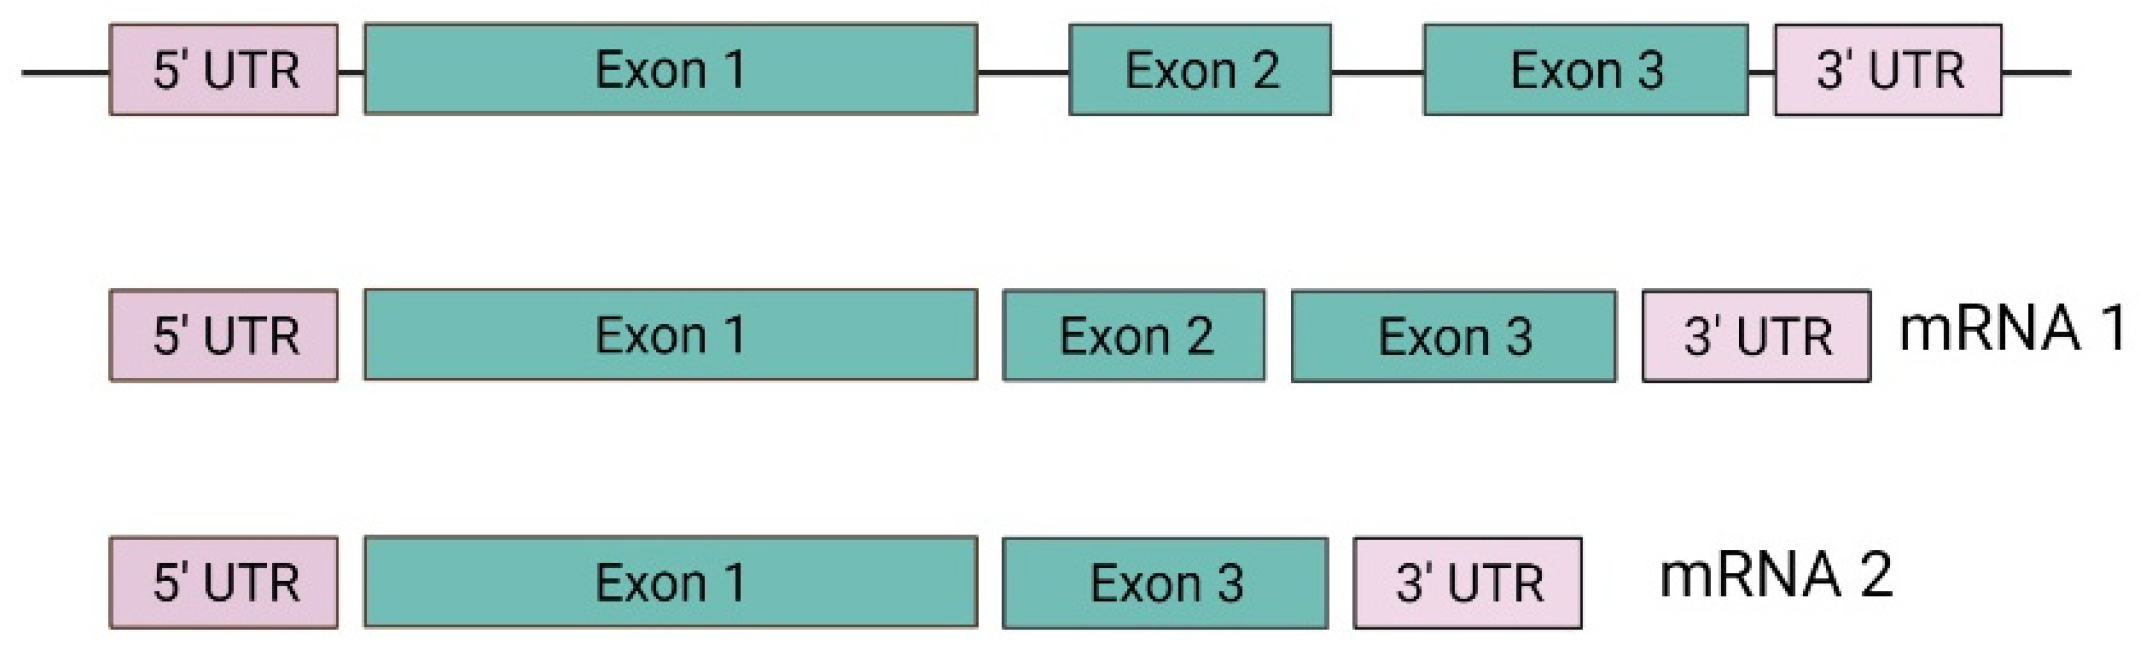

3.1. VHL Gene and Protein